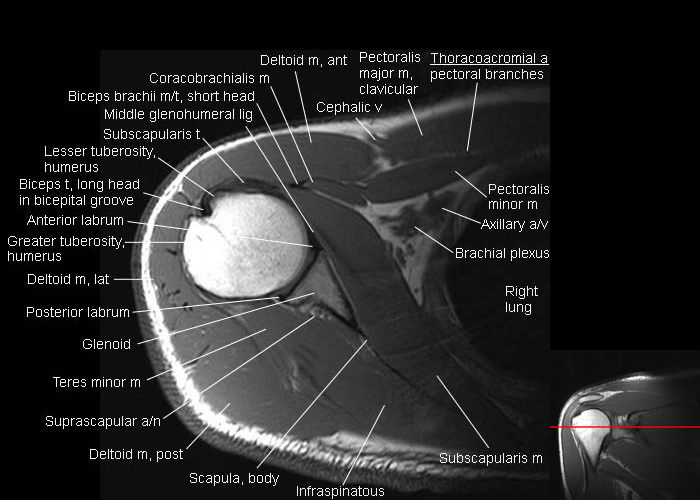

shoulder anatomy

axial